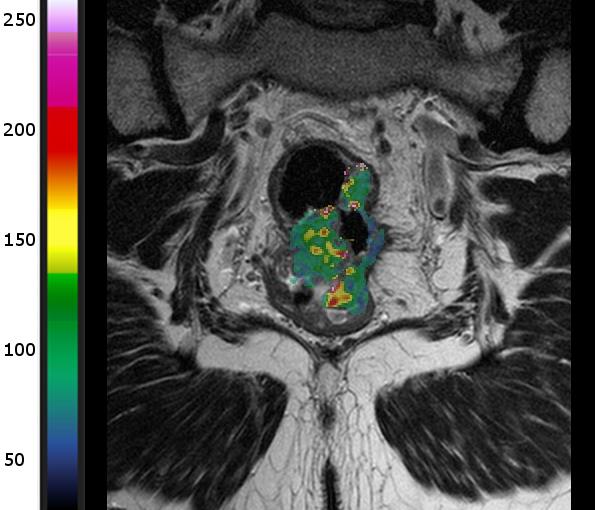

Her er MR-bilder av to ulike pasienter som har endetarmskreft i samme stadium. Den øverste har lav blodgjennomstrømning, og den nederste har høy. Den første ble diagnostisert med spredning til lever etter 12 måneder, mens den andre er sykdomsfri etter fem år. Kilde: Bakke et al. Radiology 2020